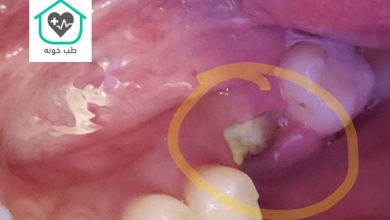

دهان و دندان